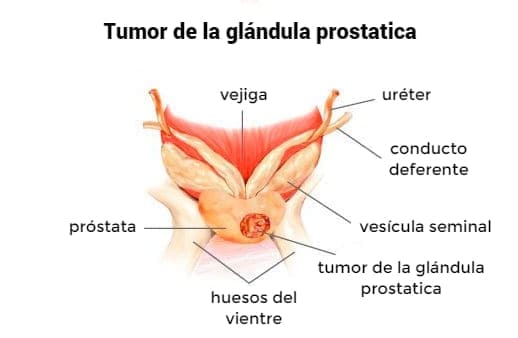

En los últimos años, las estadísticas de enfermedades urológicas han superado el número de enfermedades de los órganos circulatorios. Después de 50 años de adenoma (tumor benigno) de la próstata se encuentra en 20-25%, y a los 60 años, el 50% de los hombres. La incidencia de cáncer de próstata recientemente ha alcanzado el primer lugar entre los cánceres masculinos. Todas estas consecuencias de la disfunción eréctil progresa debido a la desnutrición. Los alimentos grasos pesados, los alimentos modificados genéticamente y el tabaco y el alcohol de baja calidad causan daños irreparables a la salud de los hombres.

- Por desgracia, sí. Muchas enfermedades masculinas, como el adenoma y el cáncer de próstata, se "vuelven más jóvenes"dramáticamente. Si antes era un problema de pacientes de edad, ahora cada vez más diagnosticamos estas enfermedades en pacientes a partir de los 40 años. Además, en los últimos 30 años, la infertilidad masculina ha aumentado muy dramáticamente. Según las estadísticas mundiales, una de cada diez parejas casadas resulta estéril, es decir, incapaz de concebir un hijo sin la ayuda de la medicina. En el 45% de los casos, el hombre es "culpable". Todo esto se debe a la disfunción eréctil, es decir incapacidad para lograr la erección necesaria para tener relaciones sexuales. Si un hombre no siempre puede lograr una erección, esto indica el comienzo cambios difíciles reversibles en su sistema reproductivo y, como resultado, abre el camino para las enfermedades concomitantes más graves, tales como prostatitis y adenoma de próstata. En el 90% de los casos, el adenoma de próstata no se puede tratar y es fatal.